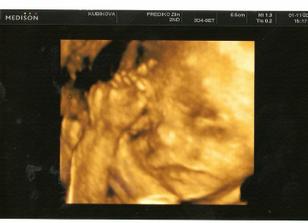

1.11. 3D ultrazvuk 🙂